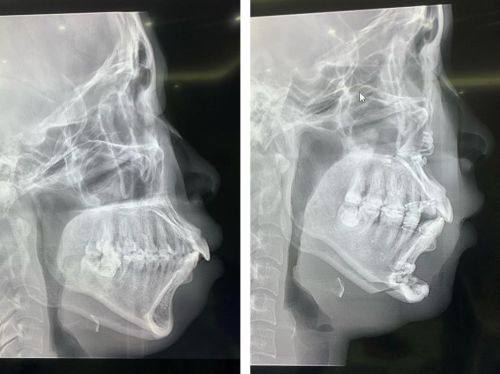

2. 口腔正畸项目:包括颌面正畸、隐形矫正等。颌面正畸可以改善患者的面部骨骼结构,解决牙齿排列不齐、咬合不良等问题,不仅能提升口腔功能,还能改善面部美观。隐形矫正则具有美观、舒适、可自行摘戴等优点,适合对美观要求较高的患者。